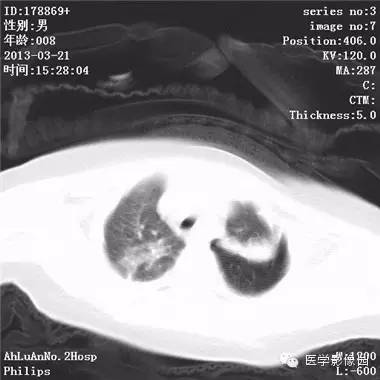

患儿男,8个月,呛咳,发热一周。实验室检查白细胞及中性粒细胞增高。

两肺肺纹理增多、增粗,右肺可见斑片状、片絮状模糊影,边界欠清;左肺上叶见楔形高密度影,内可见支气管征,尖端指向肺门;左肺下叶肺野透亮度增强;另见左肺主支气管内可见块状软组织密度影。

支气管异物(花生米)伴两肺炎症(追问病史,患儿奶奶层于一周前喂食患儿花生米,当时疑似“呛进去”,后来见好了也就没留意)。